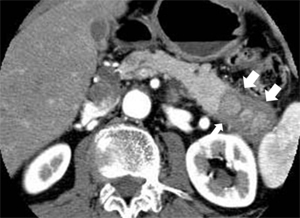

図1 自己免疫性膵炎のCT所見:

膵臓の尾部(矢印)が腫れています

超音波検査やCTで膵臓の全体的あるいは部分的な腫大が認められた場合に、自己免疫性膵炎を疑います(図1)。もうひとつの大きな画像的特徴は膵内を走行する膵管の狭細変化です。この確認のために、まず体に負担をかけずに膵管を描出できる磁気共鳴膵胆管造影(MRCP)を行い、最終的には内視鏡的膵胆管造影(ERCP)により評価します(図2)。